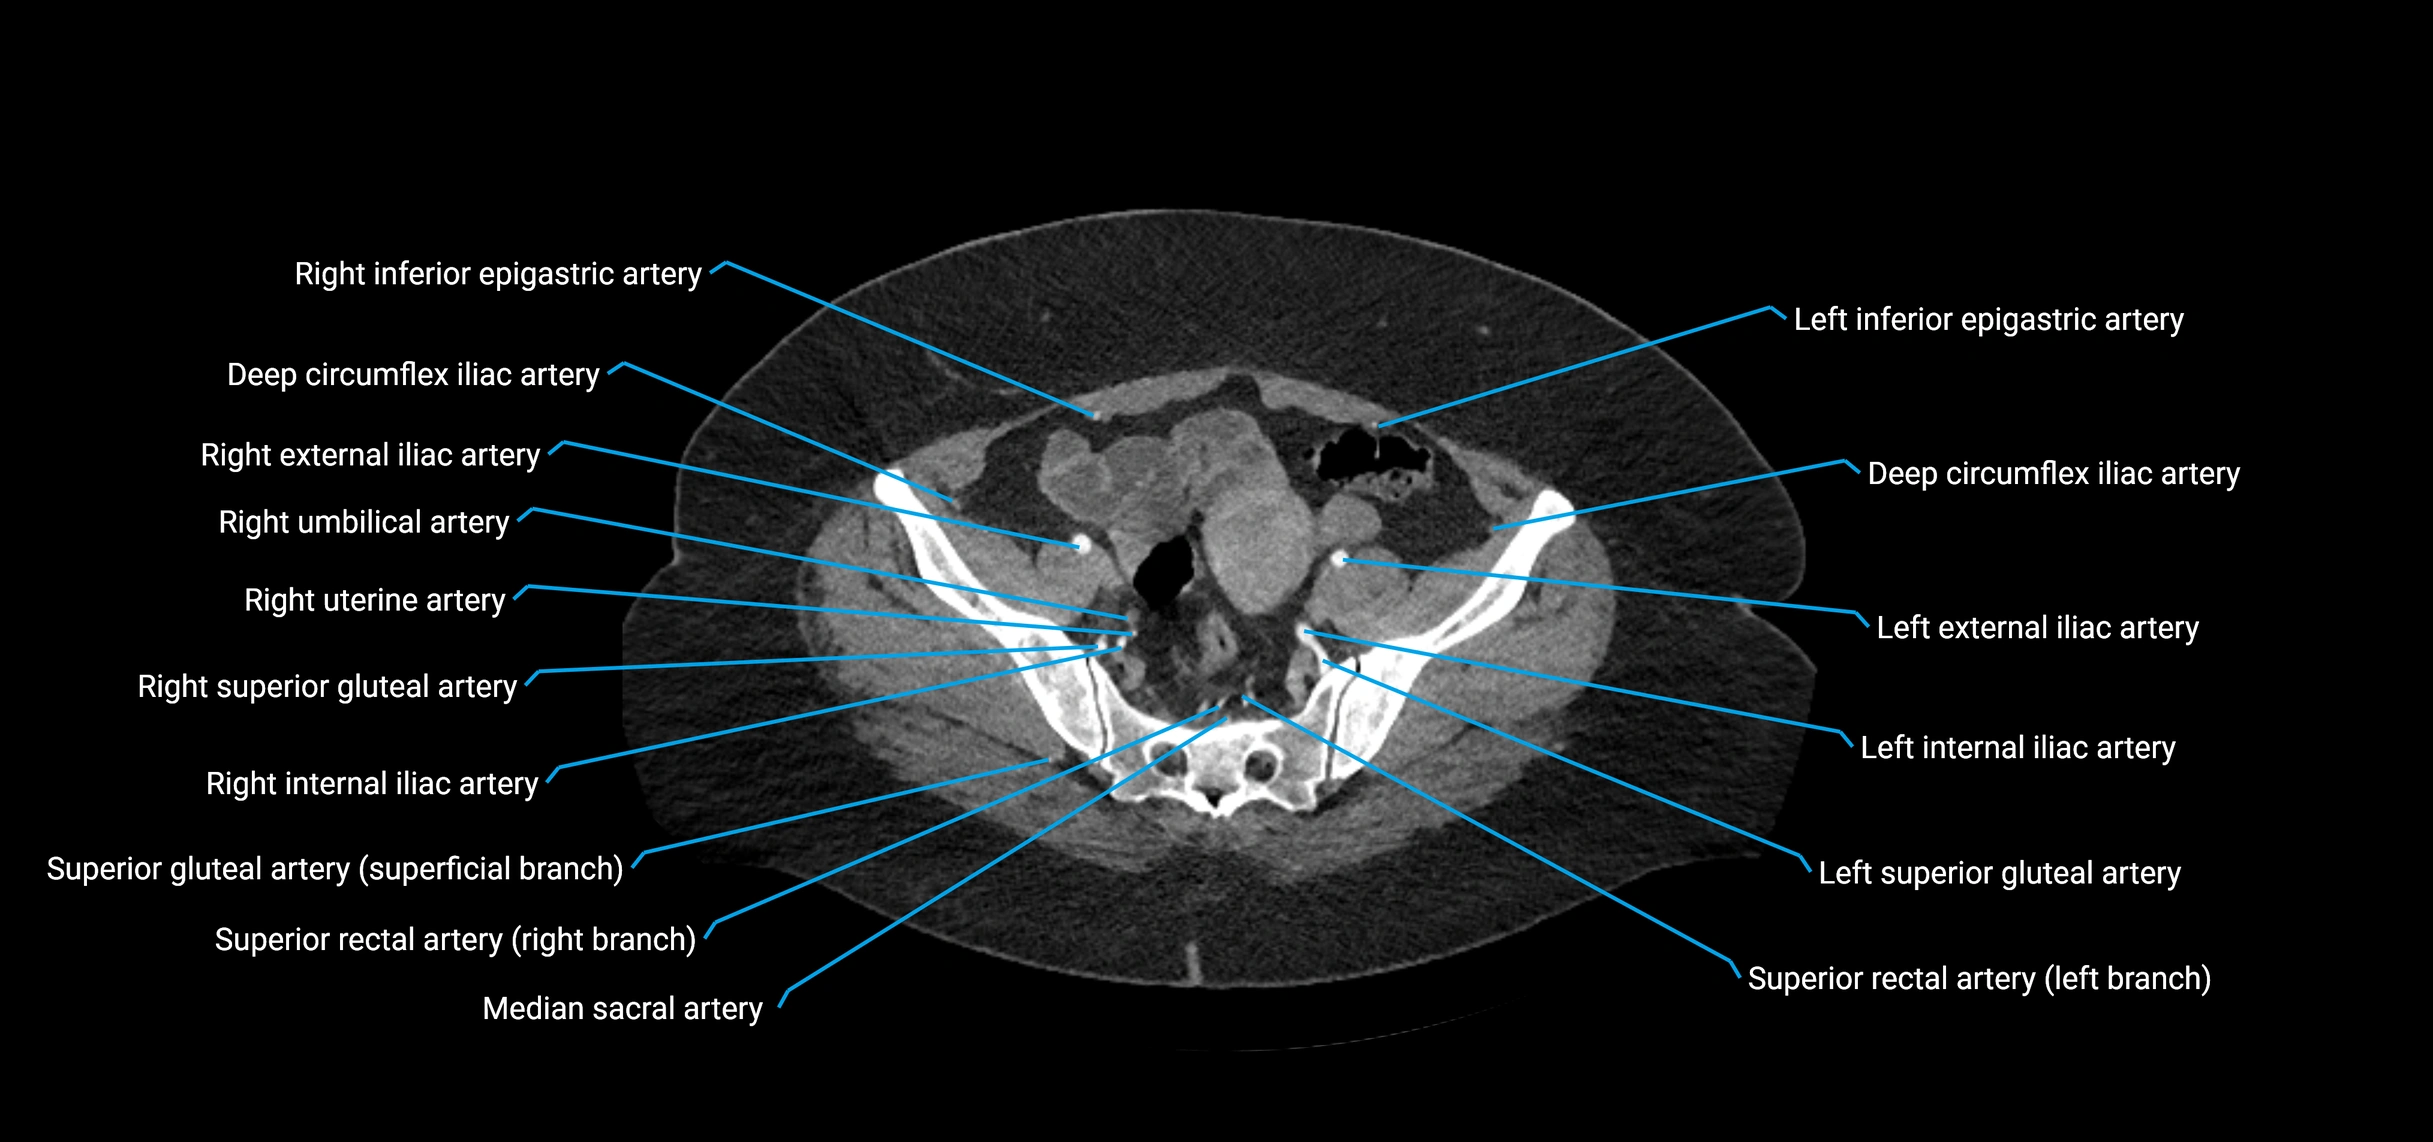

Contrast-enhanced CT (CTA):

• Gold standard for abdominal aortic imaging

• Provides excellent detail of lumen, wall, aneurysm, thrombus, and branch vessels

• Multiplanar and 3D reconstructions help in aneurysm measurement, stent graft planning, and dissection evaluation

• Detects acute rupture, traumatic injury, or occlusion with high sensitivity